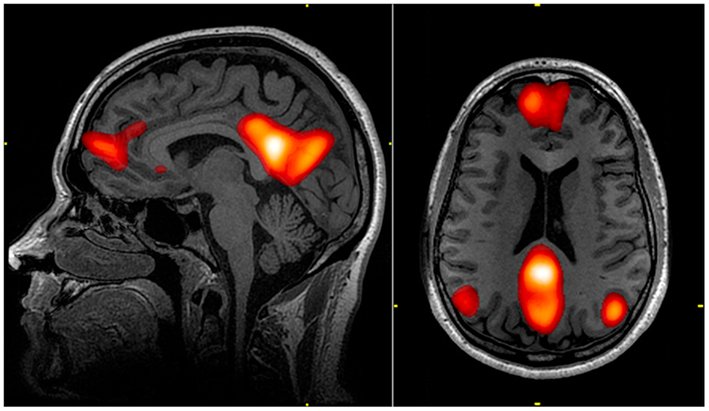

fMRI Signal

(fMRI로 찍은 뇌의 단면 예제. 연구와는 상관 없음)